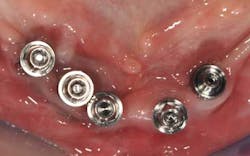

Fig. 11: For a better prosthetic outcome, the implants in site 26 and 27 have been extracted and replaced with two Biomet 3i® implants.

Fig. 12: A new implant impression is taken

Fig. 13a, b: The new master cast shows the modified implant situation

Fig. 14: Hybrid screw-retained mandibular prosthesis